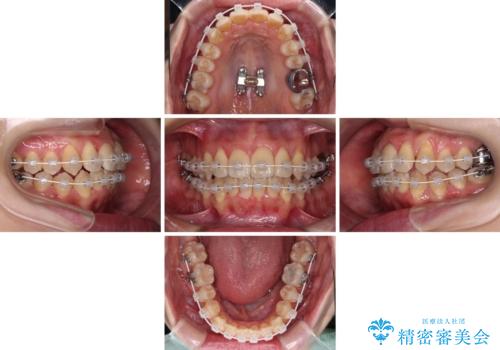

2. 治療途中

2. 【モニター】急速拡大装置 狭い歯列を拡大してワイヤー装置で短期間治療の治療中